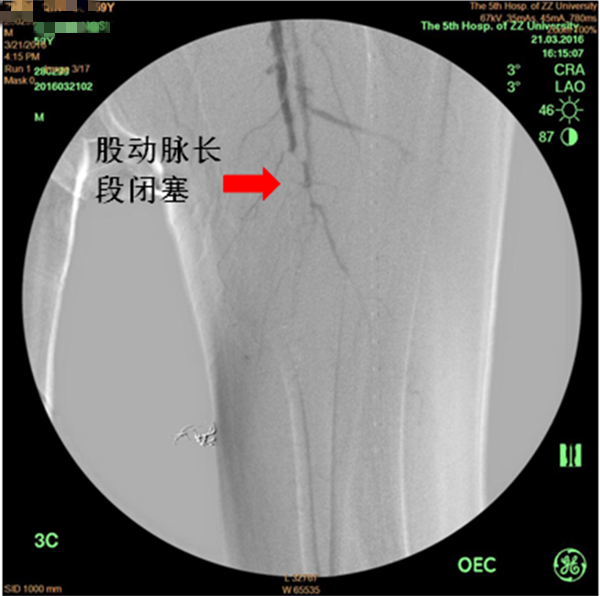

患者周先生,59岁,1年前无明显原因出现双侧小腿及足部发凉,活动后左足疼痛,3月前疼痛加重,出现左足第4及第5足趾发紫,并逐渐进展为足趾发黑、坏死,多处求医用药治疗,效果差,2周前左足疼痛进一步加重,并累及左足第3足趾发黑坏死,无法行走,严重影响了病人的生活质量(见图1)。慕名前来我院血管外科就诊。我院血管外科专家王兵教授为患者制定了详细的诊疗方案,下肢动脉CTA提示患者左侧股浅动脉多发粥样硬化斑块形成,管腔长段闭塞(见图2),明确诊断为“复杂下肢动脉硬化闭塞症”,积极术前准备后,王兵教授带领血管外科崔文军副主任、安乾主治医师、李攀峰医师给患者进行血管腔内介入治疗。术中DSA造影提示:股浅动脉长段闭塞,腘动脉通畅(见图3、图4)。单弯导管配合超滑导丝及微导丝,反复多次尝试顺行开通股浅动脉闭塞段均宣告失败,王兵教授决定采用逆穿技术,在DSA下穿刺腘动脉,成功后逆行置入单弯导管及超滑导丝,顺利开通股浅动脉闭塞段,逆行超滑导丝选入顺行单弯导管内,完成对接(见图5、图6),逆行导丝引出体外,引入球囊扩张股浅动脉闭塞段,股浅动脉闭塞段置入两枚金属裸支架后造影显示左下肢动脉全程通畅(图7、图8)。术后患者胫后动脉搏动恢复,静息性疼痛消失。 复查下肢动脉CTA:左下肢动脉血流通畅(图9)。

图3